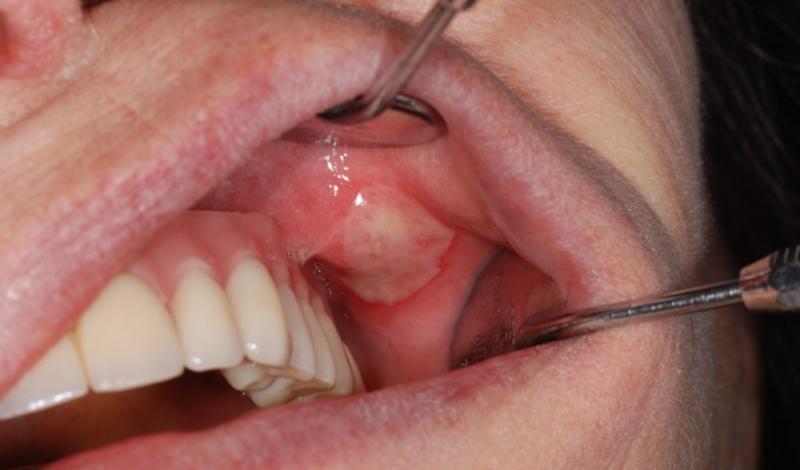

Может ли щека опухнуть от стоматита? Да, это вполне возможно. Язвенное поражение слизистой рта, особенно на щеке, обычно легко заметить, поэтому при появлении симптомов заболевания рекомендуется как можно скорее обратиться к стоматологу.

- Афтозный. Обычно возникает как реакция организма на наличие инородных объектов в ротовой полости. Язвы афтозного стоматита чаще всего формируются именно на щеке.

В зависимости от типа стоматита, течение болезни может варьироваться. Тем не менее, все формы стоматита имеют общие симптомы, которые являются достаточным основанием для срочного обращения к стоматологу:

- Щека опухла, слизистая оболочка покраснела и болит;

- На поражённой области появились гнойные язвы;

Увеличение популярности лазерной терапии объясняется её высокой точностью, отсутствием кровотечений, безболезненностью и эффективностью, что позволяет быстро и аккуратно устранить симптомы стоматита на щеке внутри рта (см. фото).